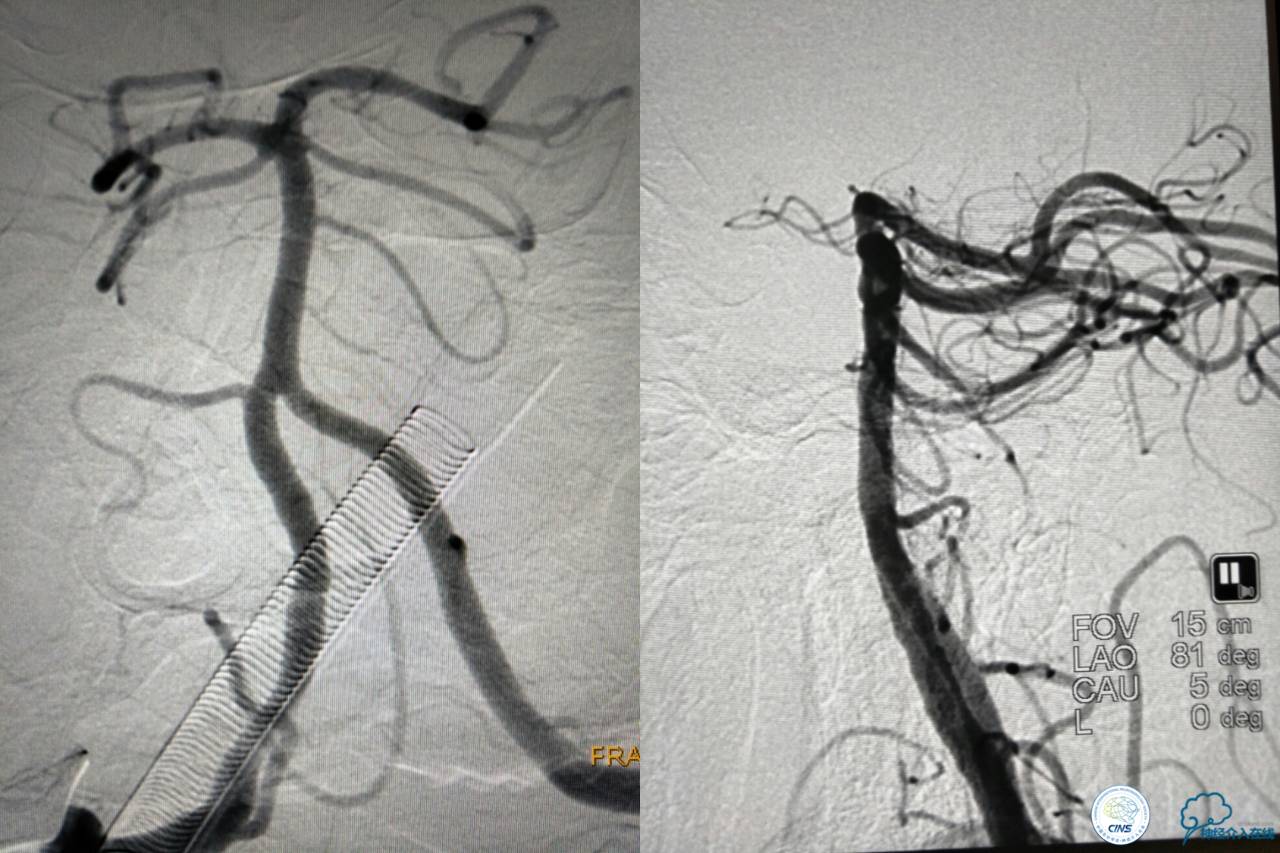

基底动脉顶端仍有大量血栓,双侧大脑后动脉未见显影,双侧小脑上动脉再通。再次取栓?还是动脉溶栓?

决定导管内给予替罗非班6ml,复查造影BA顶端仍闭塞,第二次取栓。

第二次取栓后可见基底动脉顶端仍有大量血栓,右侧大脑后动脉开通,但左侧大脑后未见显影且左侧小脑上动脉闭塞!

第三次取栓,支架放入左侧大脑后取栓。

第三次取栓后,左侧大脑后动脉开通,但是栓子再次栓塞右侧大脑后动脉,血栓在基地动脉顶端来回左右摆动,下一次,怎办?血栓负荷太多,可以使用solumbar技术,可以没有颅内导管,没办法,换用更大的支架6-20mm,但费用增加不少,与家属沟通后同意使用,第四次取栓:

血栓负荷还是很大,左侧大脑后再通,但右侧大脑后又闭塞,只能第五次取栓,支架放到右侧大脑后动脉更远。

好大的血栓,支架释放后,血管无复流,拉一把!

没错,没看错!血管成功实现再通,术中取栓的栓子如下。